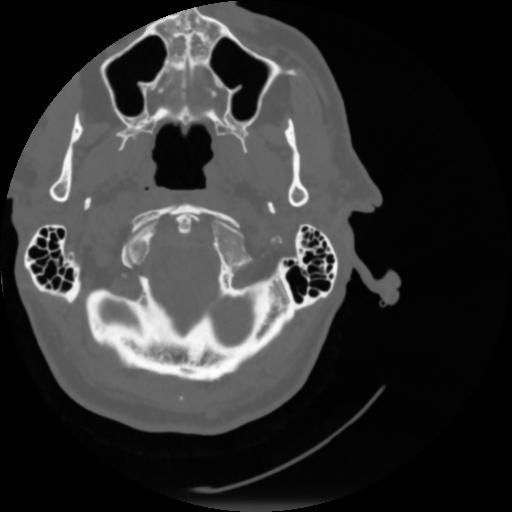

4 CEREBRO,,Vol,0.5,CEREBRO,,